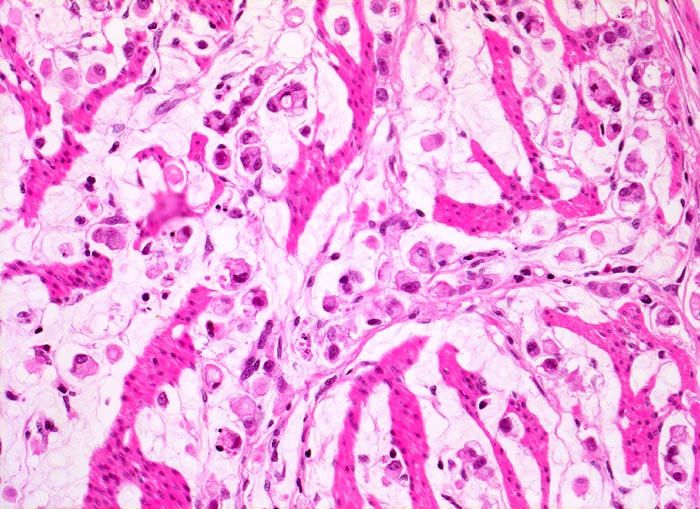

Die ersten beiden Typen entsprechen histologisch meist einem intestinalen Typ nach Lauren (> 1342). Diese Tumoren sind scharf begrenzt, bilden tubuläre oder papilläre Strukturen wie die Dickdarmkarzinome, sind meist assoziiert mit bekannten umweltbedingten Risikofaktoren und haben eine bessere Prognose.

Adenokarzinome können tubuläre, papilläre, muzinöse, siegelringzellige und undifferenzierte Anteile aufweisen, wobei die beiden letzteren besonders aggressive Tumoren darstellen.